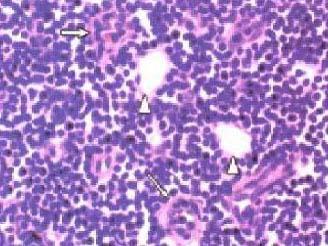

问题 正常淋巴结组织结构如图所示,不正确的叙述为 ( )

选项 A.淋巴结由淋巴细胞和网状细胞构成 B.淋巴细胞又称免疫活性细胞 C.网状细胞又称免疫辅佐细胞 D.网状细胞在演变、分化过程中不会异常增生形成肿瘤 E.淋巴细胞在演变、分化过程中会发生突变而形成肿瘤

答案 D